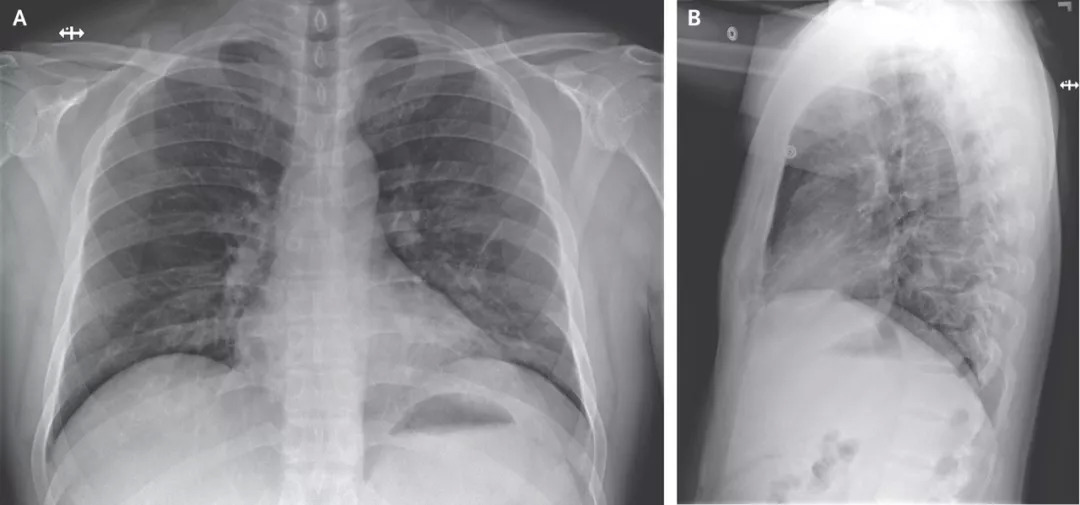

在医院第3天拍摄的胸部X光片未显示浸润或异常迹象(图三)。但是,从医院第5天晚上晚上进行的第二次胸部X光片显示,左肺下叶有肺炎的迹象(图四)。

图四

这些影像学发现与从医院第5天晚上开始的呼吸状态变化相吻合,当时患者在呼吸周围空气时通过脉搏血氧饱和度测定的血氧饱和度值降至90%。在第6天,患者开始接受补充氧气,该氧气由鼻导管以每分钟2升的速度输送。